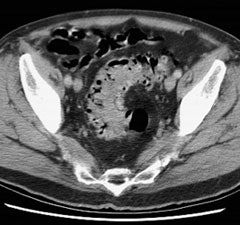

Bladder cancer: Dilute urinary activity in this patient's bladder allowed accurate detection of their bladder cancer (white arrows on CT, black arrows on PET scan). In general, urinary excretion of FDG limits evaluation of urinary tract malignancies, however, hydration and diuresis can improve diagnostic accuracy. |

|

|